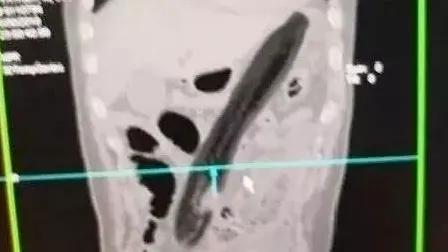

假设你是一位肛肠科医生 完全可以组织一次“直肠异物大赏”

你究竟能认出几种

塞入直肠里的异物“应有尽有”

灯泡、茄子、花露水瓶、……

甚至还有手机,千奇百怪

西南医科大学附属中医医院肛肠科主任李五生教授说:直肠异物是直肠里出现除了粪便以外的其他东西,比如灯泡、按摩棒、玻璃药瓶、陀螺、蜡烛、圆柱形金属瓶等等,甚至常见的蔬菜和长条状的物体,比如黄瓜、火腿肠、茄子、苦瓜、黄鳝、泥鳅……